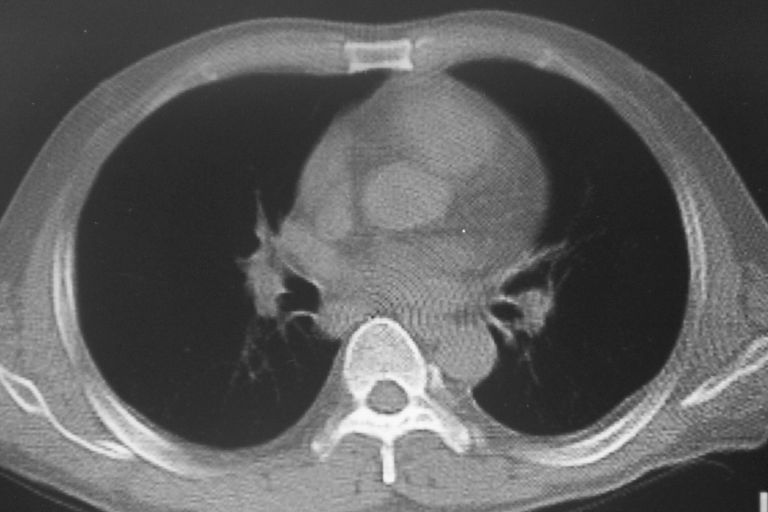

患者 男 50岁 无痛性咯血3天,无其他不适.

2心包积液

2、心包积液

2 心包积液。

左下肺结节状软组织密度影,一个边缘有卫星病灶,邻近胸膜增厚.另一个有毛刺.心影周围水样密度影环绕.考虑:

1.肺癌可能.肺tb待排.

2.左侧胸膜增厚.心包积液.